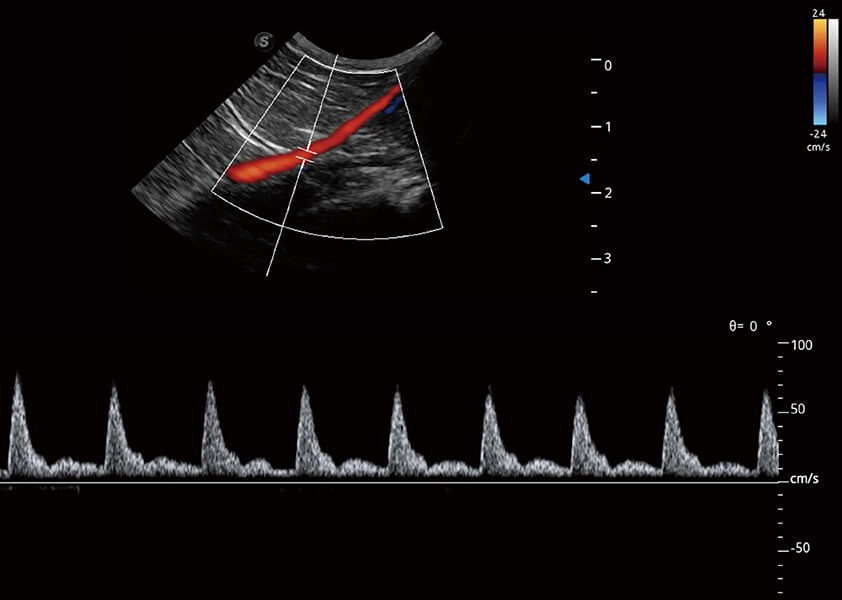

ProPet 60 作為一款高端臺式動物超聲設(shè)備,為動物醫(yī)生的日常診斷提供了一系列貼合動物臨床需求、解決臨床實際問題的高級成像功能。憑借全系列高清探頭,滿足醫(yī)生對腹部、心臟、生殖、淺表、肌骨等成像的所有需求,切實幫助您提升檢查效率,提高診斷信心。

獸用彩色多普勒超聲診斷系統(tǒng)